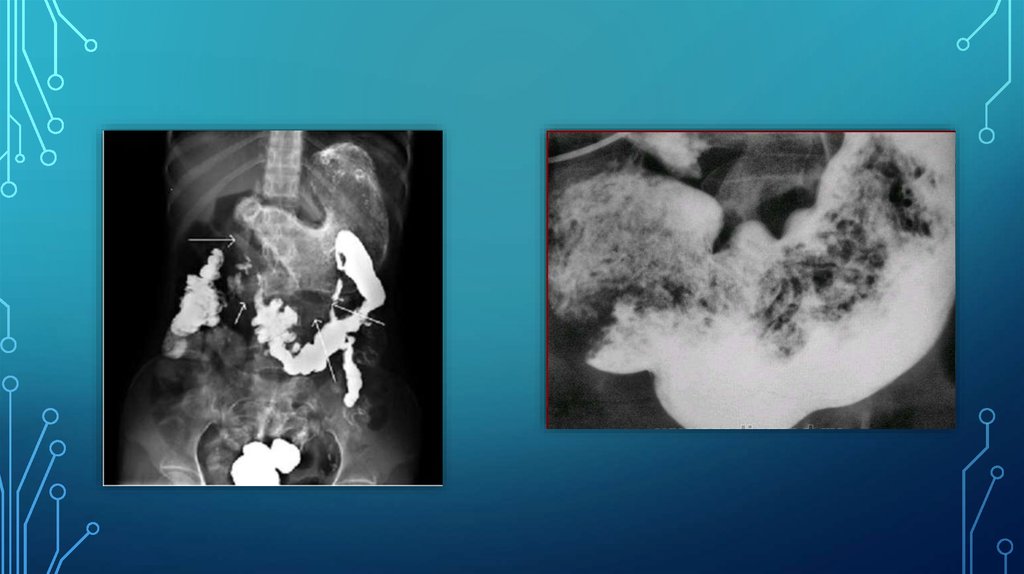

МЕТОДЫ ЛУЧЕВОЙ ДИАГНОСТИКИ

При

контрастной

рентгенографии

выявляют различной величины дефект

наполнения округлой или овальной

формы с четкими контурами, хорошо

смещаемыми при надавливании. Для

крупных безоаров желудка характерно

уменьшение размеров газового пузыря,

обтекание образования контрастным

веществом.